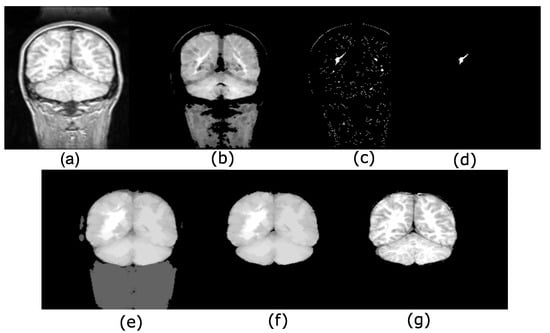

4.1. Brain Extraction Based on the Maximum Hyperconnected Function